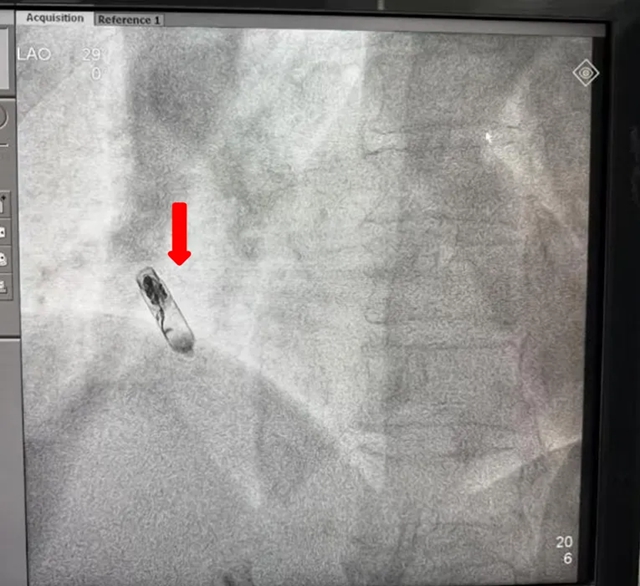

参数验证:术中实时监测显示起搏阈值、感知灵敏度等核心指标优异,设备寿命预估超10年。

植入后

注:红色箭头为无导线起搏器,黄色为递送系统

术中影像